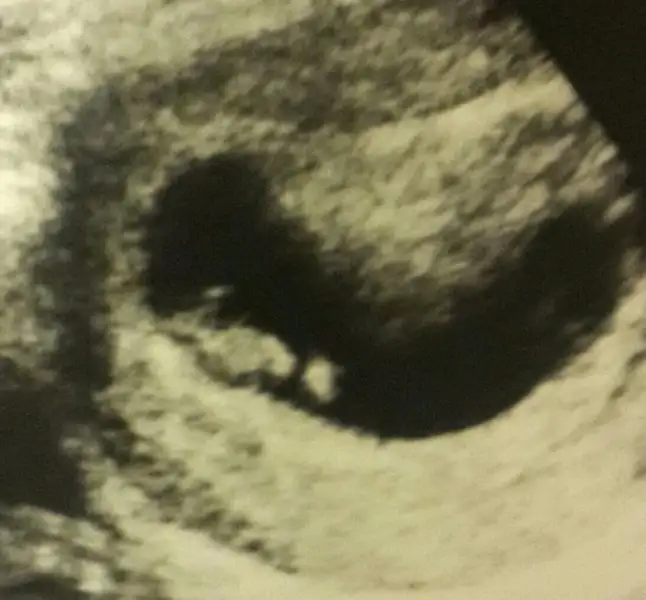

Kızlaaarrr..benim miniğime de bakarmısınız. .ben bu yöntemi pek anlamıyorum da :KK43:

Eklentiler

• 20160429_215110_Richtone(HDR)-1-1.webp

20160429_215110_Richtone(HDR)-1-1.webp

14,7 KB · Görüntüleme: 94